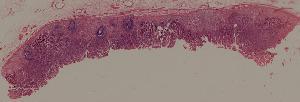

59.慢性萎缩性胃炎